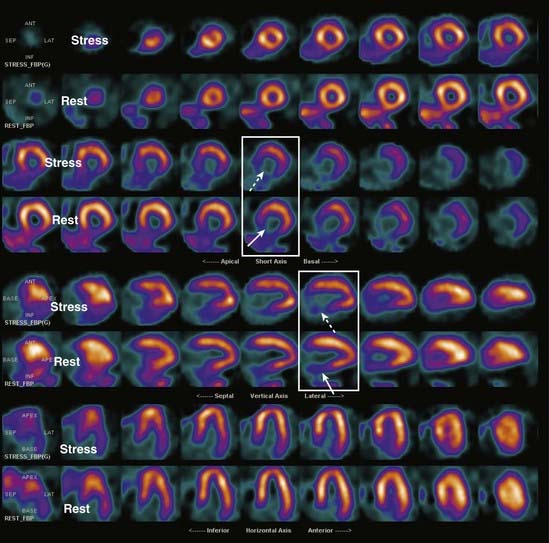

Images are displayed in a standardized format usually in color. In the short-axis view, the wall segments normally form a circle. In the vertical long-axis view, there is a U shape with the opening to the right. In the horizontal long-axis view, the opening of the U is down (Fig. 14). Wall thickness is generally uniform in the same image.

image

Figure 14 Normal cardiac scan.

Images are displayed in a standardized format, usually in color. In the short-axis view, the wall segments form a circle (white circle). In the vertical long-axis view, there is a U shape with the opening to the right (solid white arrow). In the horizontal long-axis view, the opening of the U points downward (dotted white arrow). In any given image, wall thickness is uniform. By convention, the first row of each set of images is the stress portion of the test and the second row is the rest portion of the test for those same images. Normally, each paired set of stress and rest images looks the same (white rectangles).

A nuclear scan after a myocardial infarction can demonstrate whether viable myocardium is present which, in turn, helps determine whether bypass surgery, stenting, or angioplasty will be most effective in treatment (Figs. 15 and 16).

Figure 15 Left anterior descending coronary artery ischemia.

Compare the sets of images in the two rectangles. There is a wall defect on the stress portions of the test (dotted white arrows point to thinning of the wall) which improves with rest (solid white arrows). Since the defect reverses with rest, this is more characteristic of ischemia than infarct. The defect is in the distribution of the left anterior descending coronary artery.

Figure 16 Basal inferior infarct.

Once again, compare the pairs of stress and rest images in the white rectangles. There is a fixed defect in the wall which remains on both the stress (dotted white arrows) and resting images (solid white arrows). The lack of reversibility is consistent with infarction of the inferior wall.